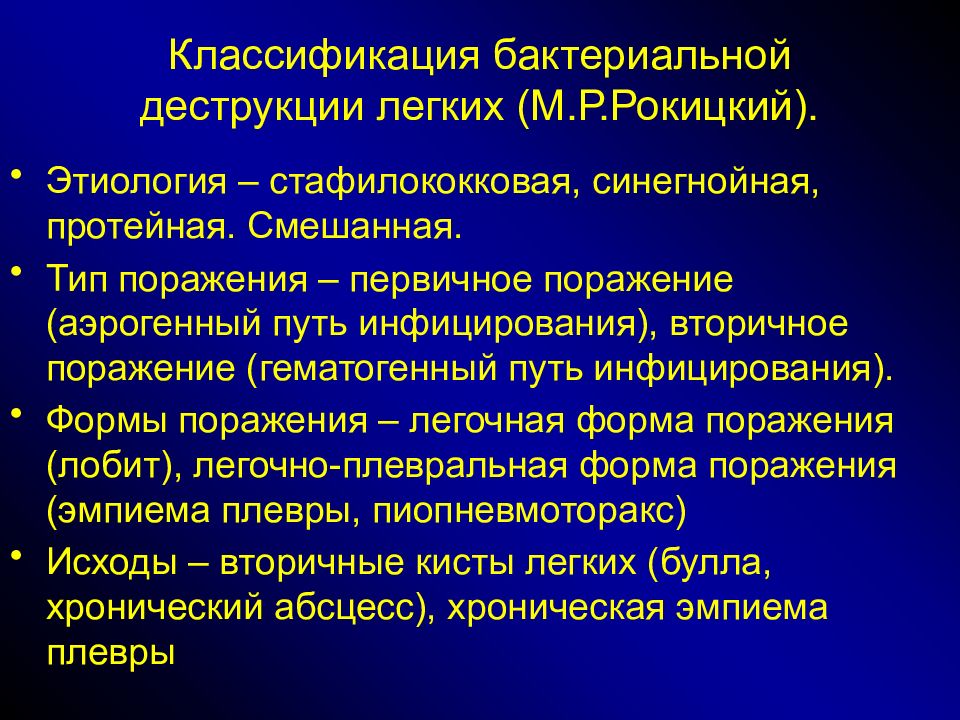

Бактериальная деструкция легких у детей презентация - 88 фото